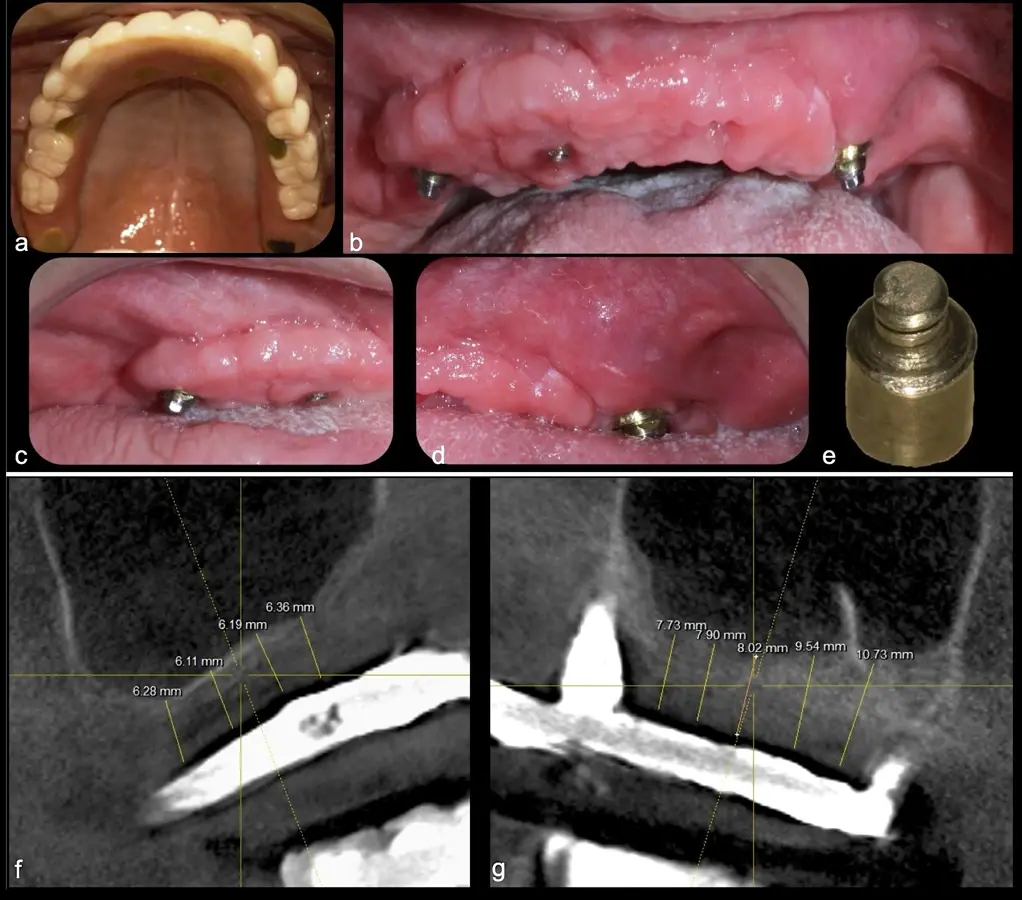

El levantamiento de piso de seno maxilar es una técnica quirúrgica aceptada previa o simultáneamente a la colocación de implantes dentales. La mayor evidencia científica refiere que si se tiene entre 0 -7 mm de altura ósea se debe realizar la elevación sinusal junto con injertos óseos; y a partir de los 8 mm, se hace más predecible la colocación simultánea de implantes dentales.1-3

La técnica se inicia con la colocación de anestesia infiltrativa, posteriormente se realiza una incisión crestal o paracrestal con posibles liberantes verticales que deben de estar alejadas por lo menos 5 mm de los límites de la futura ventana y sobrepasar la línea mucogingival. Se realiza una elevación de colgajo, se inicia la antrostomía y antroplastía. Para ello, se emplea el inserto redondo diamantado de corte al momento de delimitar los bordes de la ventana de acceso. Luego se cambia al inserto aserrado liso de calibre fino con superficie diamantada, para profundizar y eliminar el hueso en el contorno de la ventana. Una vez que se traslucen los tejidos, se puede optar por el retiro de la tapa ósea o el levantamiento de ésta junto con la membrana.

El tipo de inserto a ser utilizado dependerá del espesor de la pared ósea. Si la pared es menor a 0.5 mm, es mejor utilizar insertos de desgaste para prevenir la ruptura de la membrana de Schneider; si el espesor es mayor a 0.5 mm, se puede utilizar insertos de corte de espesor medio (Figura 3).

El clínico puede retirar la tabla ósea o introducirla como “tienda de campaña” dentro del seno maxilar. En cualquiera de las alternativas, es importante evaluar la presencia de tabiques óseos y de la arteria postero alveolar superior.